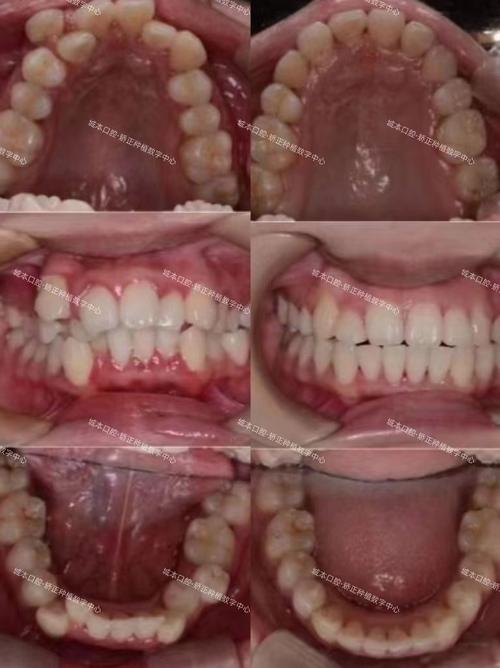

轻度拥挤的临床表现多样,前牙区可见牙齿轻微扭转、邻面稍重叠,牙弓弧度稍不规则,部分患者可能出现刷牙时局部牙龈轻微红肿、食物嵌塞,或微笑时牙齿排列不自然,但对咀嚼功能影响较小,患者常因美观需求或医生建议就诊。

矫正方法需根据患者年龄、拥挤程度、美观需求及口腔条件综合选择,传统金属托槽矫正性价比高,适用范围广,通过弓丝与托槽施加轻微力量移动牙齿,但美观性稍差;陶瓷托槽颜色接近牙齿,兼顾美观与强度,适合对美观要求较高的患者;隐形矫正采用透明牙套,可自行摘戴,舒适度高且不影响社交,但需患者高度配合,按时佩戴;舌侧矫正将托槽粘于牙齿内侧,完全隐形,但对技术要求高,价格昂贵,适应症相对局限,不同矫正方式特点对比如下: